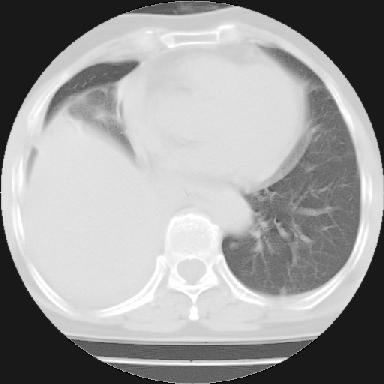

以下是引用苯小孩在2007-4-13 16:20:00的发言:[br]1、右下肺中央型肺癌并阻塞性肺不张、肺内转移、胸椎右侧附件亦有转移<横断层面第8层>.[br]2、右侧胸腔积液.

以下是引用swyyy2007在2007-4-13 15:31:00的发言:[br]右肺门下区肿块,右肺下叶支气管阻塞,右肺下叶不张,右侧大量胸腔积液,右肺中叶见结节状高密度影,边缘清,纵隔内见肿大淋巴结。首先考虑右下肺中心型肺癌伴右肺下叶不张、中叶、纵隔淋巴结转移。右侧胸腔积液。